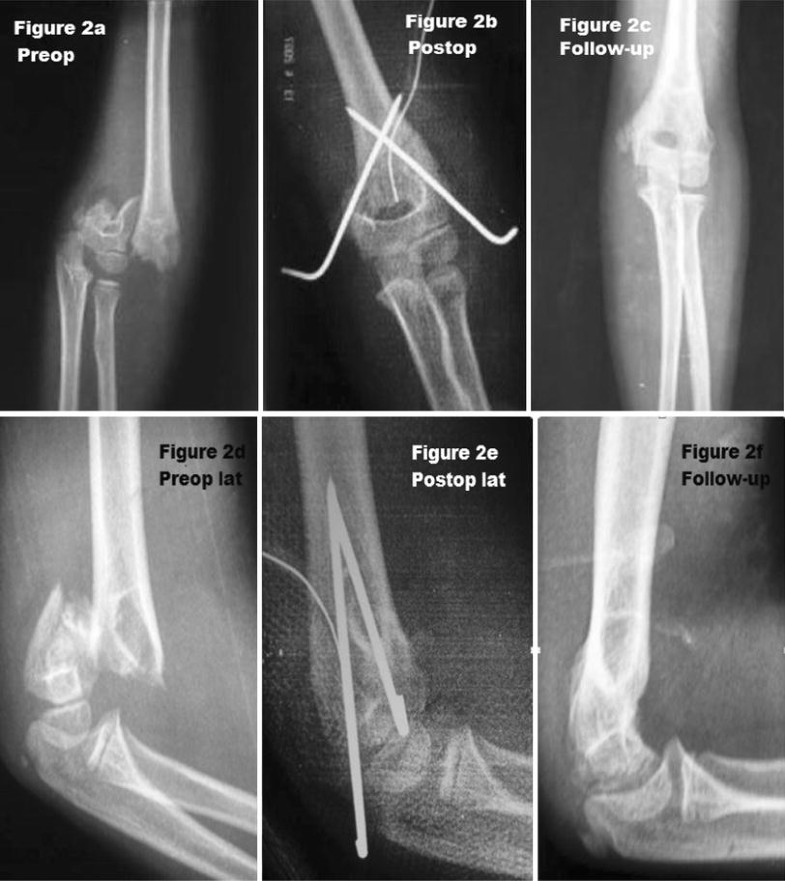

Figure 2 from The Reduction Maneuver for Pediatric Extension Type 3 Extension Type Supracondylar Fracture 95% are extension type (foosh mechanism) clinical features. Distal humerus fractures are traumatic injuries to the elbow that comprise of supracondylar fractures, single column fractures, column fractures or coronal shear. Most common elbow fracture in patients age <8yr. The majority of all extension type supracondylar fractures show a rupture of the anterior (cubital) and medial periosteum (as shown in these. Extension Type Supracondylar Fracture.

Figure 2 from Management of displaced extensiontype supracondylar Extension Type Supracondylar Fracture Distal humerus fractures are traumatic injuries to the elbow that comprise of supracondylar fractures, single column fractures, column fractures or coronal shear. Supracondylar fractures are initially divided into two types, depending on the direction of displacement of the distal fragment: Most common elbow fracture in patients age <8yr. 95% are extension type (foosh mechanism) clinical features. The majority of all. Extension Type Supracondylar Fracture.